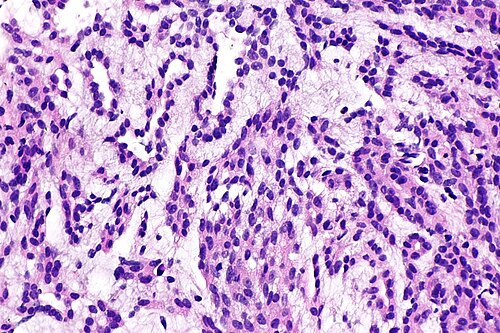

4

Diagnosis?

Renal oncocytoma -- high mag.jpg

Angiomyolipoma

Benign kidney

Chromophobe renal cell carcinoma (classic)

Chromophobe renal cell carcinoma (eosinophilic)

Clear cell papillary renal cell carcinoma

Clear cell renal cell carcinoma

Collecting duct carcinoma

Cystic nephroma/mixed epithelial stromal tumour

HLRCC syndrome associated RCC

Hybrid oncocytic/chromophobe tumour

Metastatic carcinoma

Mucinous tubular and spindle cell carcinoma

Oncocytoma

Papillary renal cell carcinoma

Renal cell carcinoma, unclassified

Renal medullary carcinoma

Succinate dehydrogenase-deficient renal cell carcinoma

t(6;11) translocation carcinoma

Tubulocystic renal cell carcinoma

Urothelial carcinoma

Wilms tumour

Xanthogranulomatous pyelonephritis

Xp11.2 translocation carcinoma